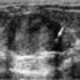

Sclerosing cemental mass